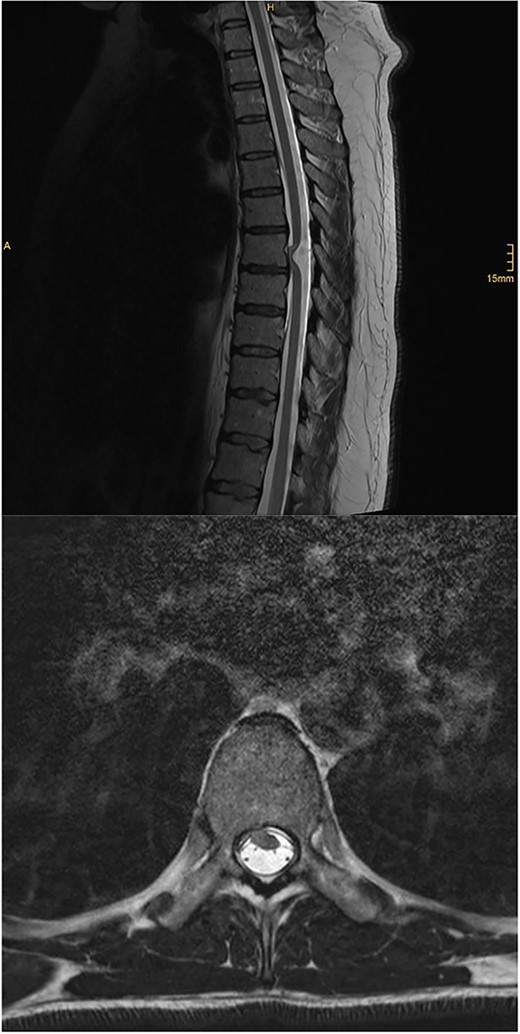

MRI of the brain (see Fig. 1) revealed features of low intracranial pressure. An MRI of the spine (see Fig. 2) revealed focal thoracic herniation of the ventral cord through the thecal sac with CSF signal in the anterior epidural space. No cord signal abnormality was demonstrated. Neurological examination was unremarkable with no numbness or weakness of the lower limbs.

Illustrative sagittal gadolinium enhanced T1 MRI of the brain demonstrating the sequalae of intracranial hypotension, the likes of which may be precipitated by a ventral spinal dural defect; there is smooth pachymeningeal enhancement, partial effacement of the cortical sulci, sagging cerebellar tonsils, a full appearing pituitary gland and slight prominence of the straight sinus; illustrative sagittal gadolinium enhanced T1 MRI of the brain, demonstrating the sequalae of intracranial hypotension, the likes of which may be precipitated by a ventral spinal dural defect; case courtesy of Behrang Amini, from the case rID: 36019 (https://radiopaedia.org/cases/36019?lang=gb)